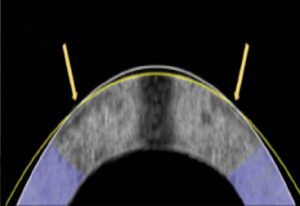

机电重新形成将这只兔子的角膜从它的原始形状(白色线条)压平至一个矫正后的形状(黄色线条),如图所示。(Image credit: Daniel Kim and Mimi Chen)

研究人员在12只兔子的眼球上测试了这种方法,其中10只被治疗宛如它们有近视或远视一样。这种治疗以一种更好聚焦在视网膜上的方式成功地重新形成了角膜,眼球中的细胞在这个过程中没有受到损伤。